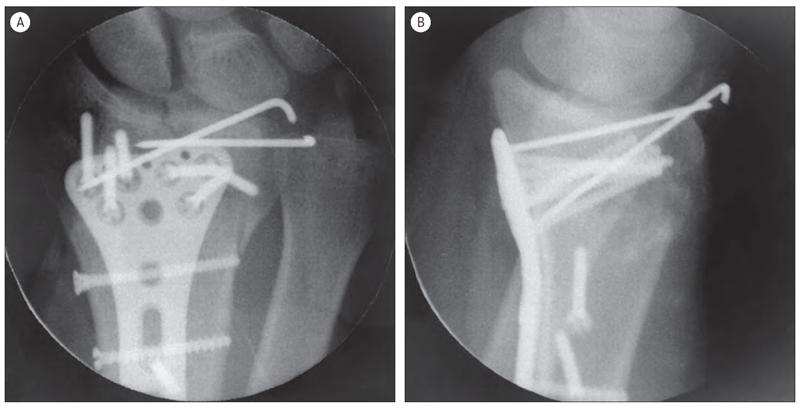

41 gadu vecam pacientam ar augstas enerģijas traumu pirms ārstēšanas uzsākšanas veikta rentgenogramma (sk. 5. A, B att.). Traumas dienā veikta lūzuma fiksācija ar ĀFA (sk. 6. att.), pēc piecām dienām – lūzuma osteosintēze ar volāro kompresijas plāksni un stieplēm plaukstas artroskopijas kontrolē (sk. 7., 8. att.). Pēcoperācijas rentgenogrammā redzama locītavas virsmu kongruences restaurācija abās standarta projekcijās (sk. 9. A, B att.).

5. attēls. Rentgenogramma traumas dienā / | 6. attēls. Rentgenogrammā – aina pēc ĀFA uzlikšanas / X-ray after external fixation |

9. attēls. Pēcoperācijas rentgenogrammas / X-ray after the surgery